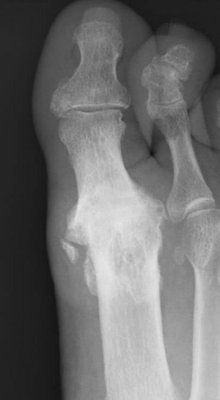

Hallux rigidus ist die medizinische Bezeichnung für eine Arthrose im Großzehengrundgelenk.

Diagnostik

Notwendig ist eine exakte Diagnose der Veränderung! Der Fuß muss angesehen, angefasst und

geröntgt werden. Notwendig sind Röntgenbilder in mehreren Ebenen unter Belastung. Häufig muss zusätzlich eine Sonografie und eine Fußdruckmessung durchgeführt werden. In Ausnahmefällen ist eine Kernspintomografie erforderlich.